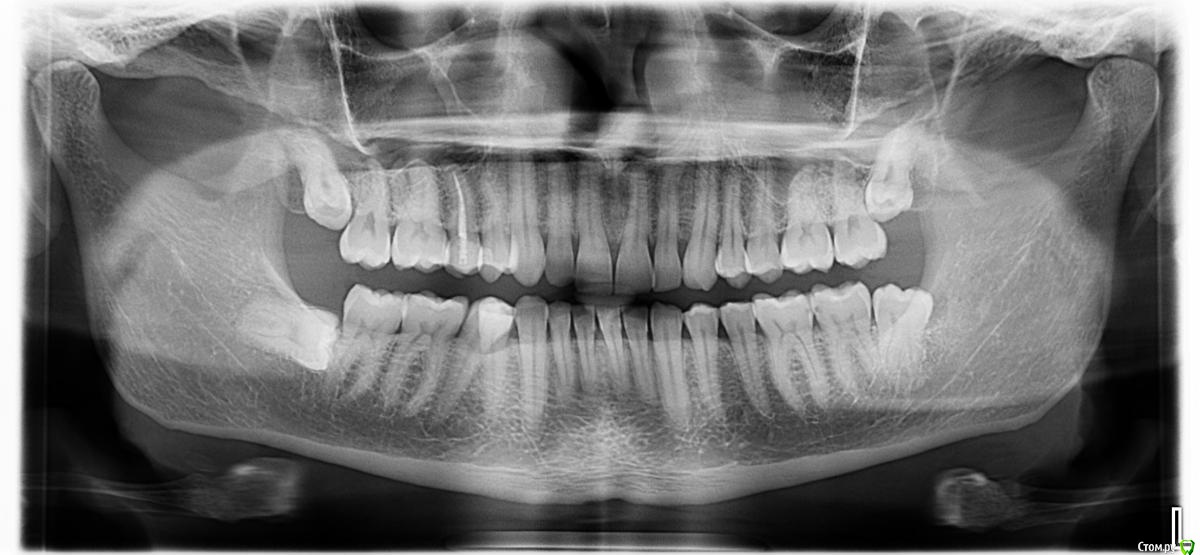

Anatolysn Опубликовано 19 мая, 2020 Поделиться Опубликовано 19 мая, 2020 (изменено) Добрый день, подскажитепо КТ это какая стадия кариеса?средняя или глубокая?https://cloud.mail.ru/public/56CB/2NFWVt9Gd справа второй и третий коренные зубы нижней челюсти Изменено 19 мая, 2020 пользователем Anatolysn Ссылка на комментарий

АнтонТЛТ Опубликовано 19 мая, 2020 Поделиться Опубликовано 19 мая, 2020 Снимок является дополнительным методом исследования, а не основным. По нему кариес скорее средний. По факту при лечении (когда удаляются размягченные ткани зуба) может оказаться глубоким. 3 Ссылка на комментарий